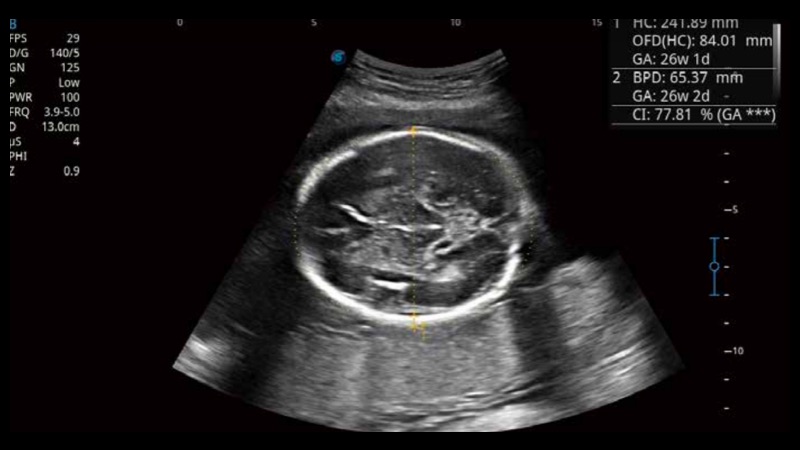

S-Fetus基于大數(shù)據(jù)深度學習算法,能夠幫助您在產(chǎn)前篩查過程中智能識別胎兒標準切面、自動測量并錄入報告。一個按鍵,即可智能、精準、高效地獲取胎兒生理指標,極大簡化您的產(chǎn)科檢查操作。

可快速對產(chǎn)科掃查切面完成胎兒生理學參數(shù)的自動測量,減少操作者按鍵次數(shù),大幅提升檢查效率。

自動識別頸項透明層并獲得NT值,為早孕胎兒畸形篩查提供有效測量工具,提高診斷效率和診斷信心。